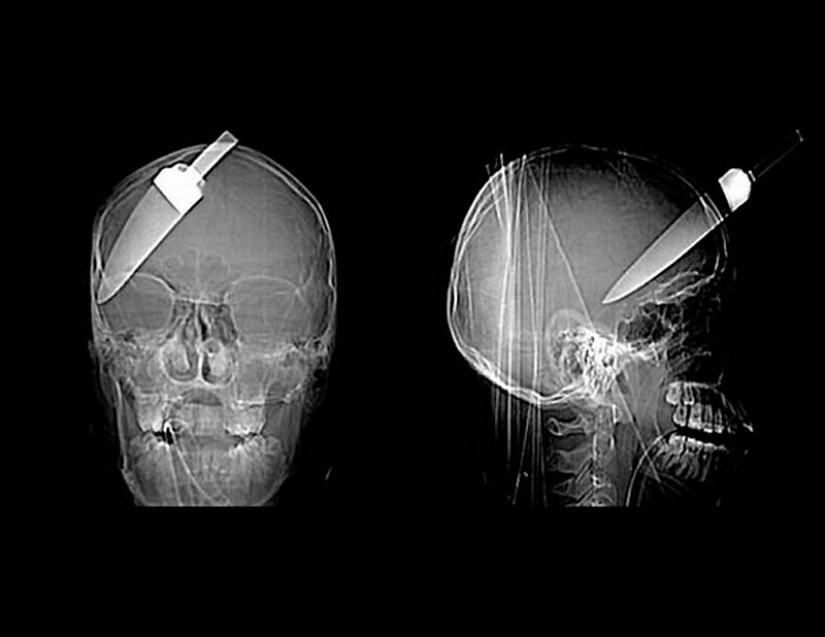

15. Cuchillo en la cabeza de niño de 10 años. El niño sobrevivió.

18. 12 centímetros de cuchillo en el cráneo de un adolescente.